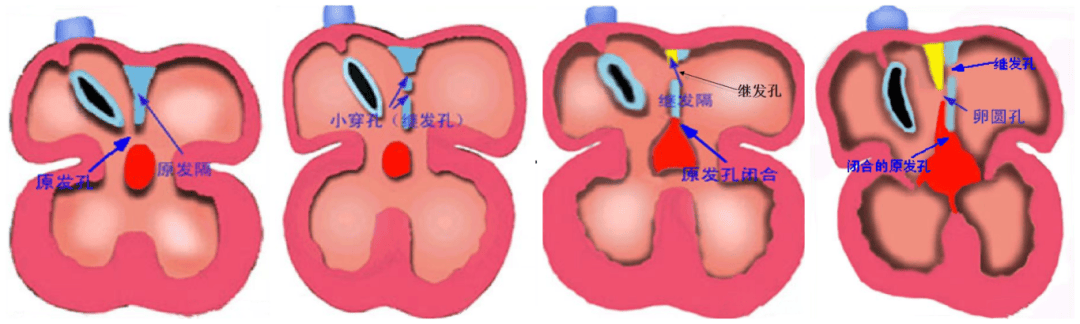

房间隔缺损(Atrial Septal Defect, ASD)是较常见的一种先天性心脏病,由于胚胎期房间隔发育、吸收或融合异常,导致左右心房之间残留未闭的房间孔。房间隔缺损可单独存在,或与其他心血管畸形合并存在。

房间隔缺损是由原发隔和继发隔组成,原发隔位于左侧,继发隔位于右侧。

一、病理分型

房间隔缺损分原发孔型与继发孔型,通常房缺是指继发孔型。根据缺损部位不同分为四型:

中央型又称卵圆窝型:位于房间隔中部相当于卵圆窝部位,此型最常见,76%;

下腔型:缺损位于房间隔后下方,与下腔静脉入口相延续,12%;

上腔型:位于房间隔后上方,缺损与上腔静脉入口无明确界限,3.5%;

混合型:兼有上述两种以上的巨大房间隔缺损,8.5%。